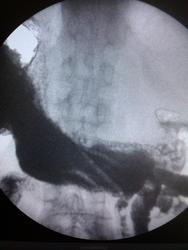

Пациент, 59 лет. Направительный диагноз: заболевание желудка? Жалобы на боли в эпигастрии, слабость, снижение памяти, отсутствие аппетита, одышку. Алкогольная зависимость 2 ст. На ФГДС: полип в верхнем трети тела желудка.. Какие будут мнения?

Что-то мне свод желудка не нравится

Да, какой-то он деформированный, хотя на 5 снимке вроде расправляется при раздувании, наверное складки такой эффект дают. А на 3-ем наверное тот полип

Есть изменения антрального отдела. Как с перистальтикой?

Свод желудка типичное не то, на всех снимках есть патологические изменения. На ФГДС могли просто недостаточно исследовать этот отдел

Если Вы укажите на смущающий Вас полип, я нарисую Вам дивертикул и скажу, что признаки есть за бульбит...